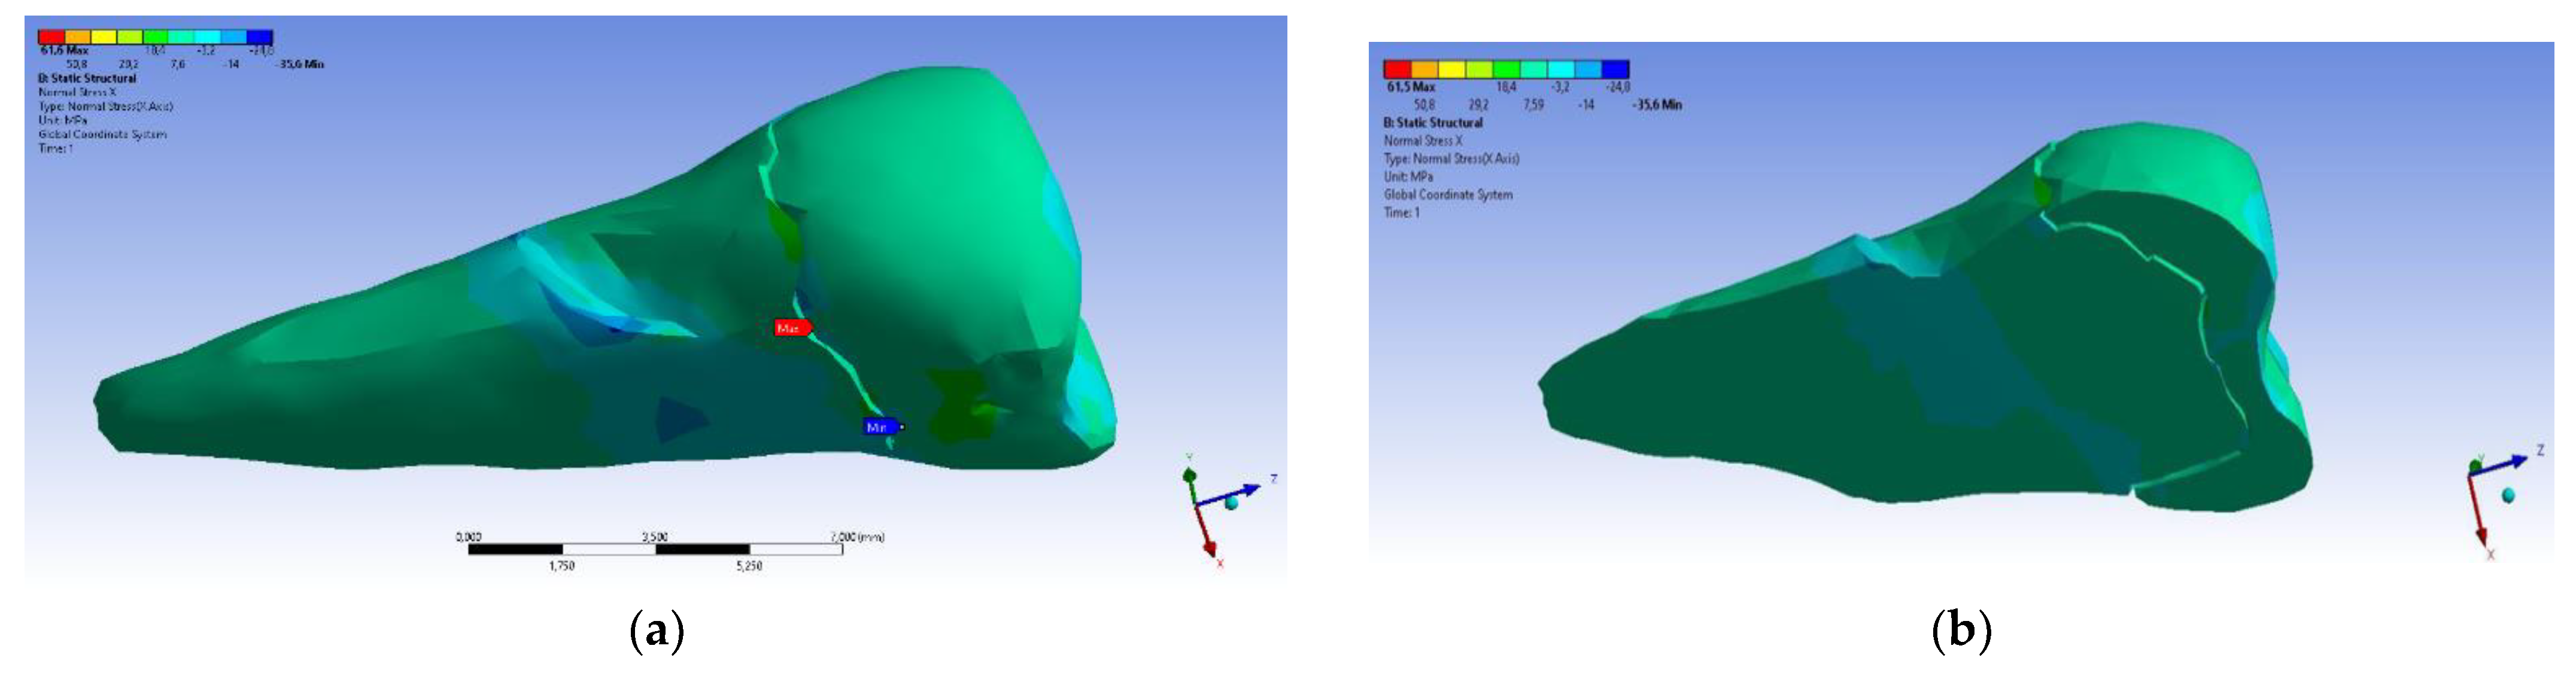

3. Finite Element Analysis (FEA) of Mandibular Right Premolars

| Total Deformation | Deformation in X Direction | Deformation in Y Direction | Deformation in Z Direction | Equivalent Stress | Normal Stress X | Normal Stress Y | Normal Stress Z | Maximum Main Stress | Minimum Main Stress | Tangential Stress XY | Tangential Stress YZ | Tangential Stress XZ | |

|---|---|---|---|---|---|---|---|---|---|---|---|---|---|

| Minimum | 0 mm | −4.24 × 10−3 mm | −2.52 × 10−2 mm | −1.56 × 10−2 mm | 1.01 × 10−6 MPa | −35.6 MPa | −57.1 MPa | −104 MPa | −15.2 MPa | −152 MPa | −43.7 MPa | −39.6 MPa | −56.3 MPa |

| Maximum | 2.77 × 10−2 mm | 3.57 × 10−3 mm | 6.98 × 10−4 mm | 4.78 × 10−3 mm | 248 MPa | 61.5 MPa | 177 MPa | 72.2 MPa | 195 MPa | 21.4 MPa | 44.2 MPa | 117 MPa | 22.2 MPa |

| Minim. in | Cementum | Cementum | Enamel | Enamel | Cementum | Cementum | Enamel | Enamel | Enamel | Cementum | Enamel | Enamel | Cementum |

| Maxim. in | Enamel | Enamel | Cementum | Enamel | Cementum | Enamel | Enamel | Enamel | Enamel | Enamel | Cementum | Cementum | Cementum |